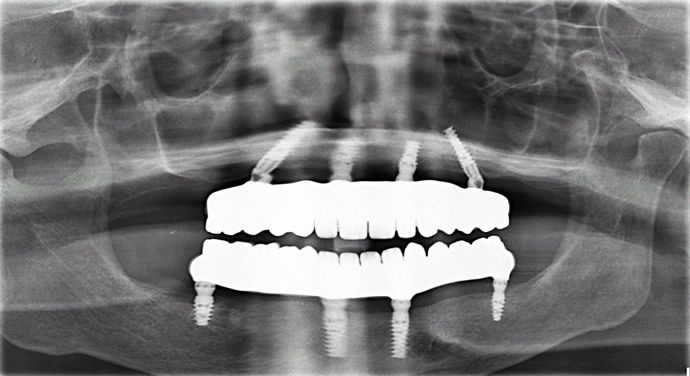

All-on-4/ Full Mouth Dental Implants / Teeth in a Day: Case 7-BB- Upper and lower All-on-4 bridges

Procedures : extractions, implants, All on 4 , Teeth in a day, no bone grafting and full mouth reconstruction with monolithic zirconia bridges.